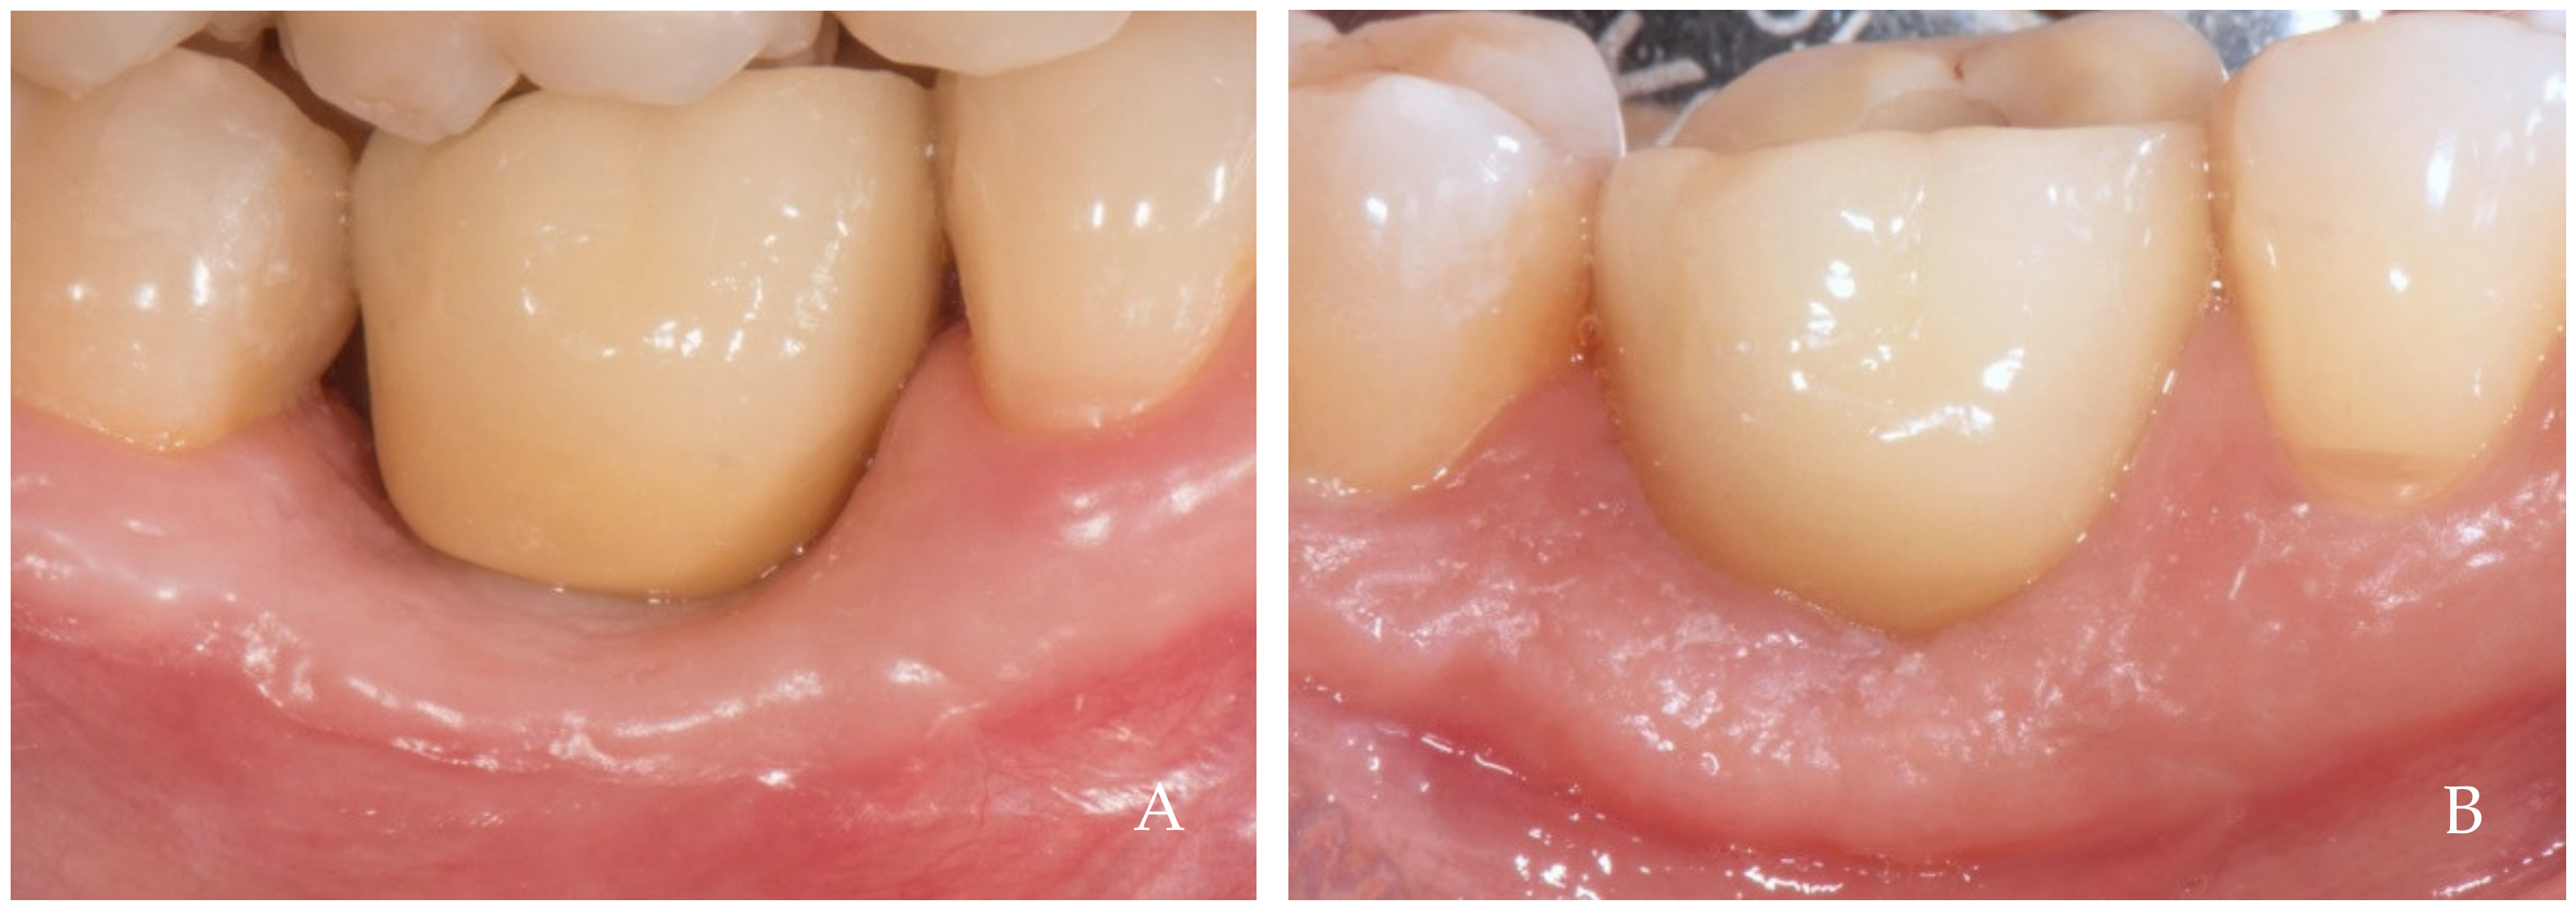

2. Clinical Examples of Oral Soft Tissue Growth